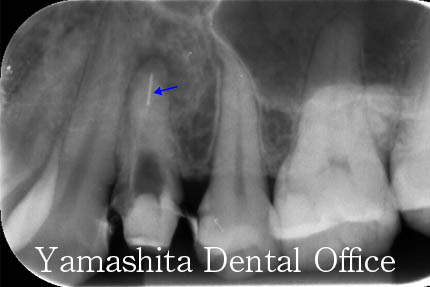

根の先に大きな黒い影(病巣)があります。前医による器具の操作により根の先に穴が開いてしまっており(パーフォレーション)、骨に細菌感染を起こすと共に、根の中につめるお薬が骨の中に飛び出してしまっています。

途中経過です。根の先からお薬が飛び出ているのがよくわかると思います。マイクロスコープを使用し、丁寧にかき出して行きます。この歯は根の管の数が4本もある特殊な状態でした。4本とも全てパーフォレーションしている状態でした。